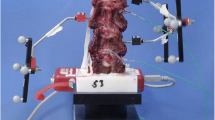

Set-up for the mechanical tests on the sheep and human cervical spine models: a testing set-up of an intact cervical spine; b cadaveric specimen of a sheep cervical spine; c cadaveric specimen of a human cervical spine; d the testing set-up of the fusion cervical spine; e pressure mapping sensor; f designed model of the non-grafted interbody fusion cage; g printed PEEK interbody fusion cage

A multi-functional joint simulator (VIVO, AMTI, USA) (Fig. 3a) was employed to provide the specified loading and motion, simulating those of the natural spine with a maximum load magnitude of 4.5 kN along the Z direction, a maximum flexion angle of ± 100° along the X direction, a maximum abduction angle of ± 30° along the Y direction, and a maximum rotational motion of ± 40°. According to the set-up of the intact SCS model, the load of a bending moment of 2.5 Nm was applied towards the X+ direction at a rate of 5.0 Nm/min until up to 2.5 Nm (DeVries et al. 2012) to simulate lateral bending in response to the X+ motion of the spine. Under such a loading environment, the C3–C4 vertebral body specimens were forced to bend laterally and then fully recovered their natural posture when the loading system was withdrawn. Other motions, such as lateral bending in the X−, Y+, and Y-directions and rotational motion along the Z direction, could be implemented in the same manner (Fig. 3b). The maximum angular displacements of C3 relative to C4 were recorded when the exerted loading magnitudes reached their maximum value, and those displacements were taken as the range of motion (ROM) of the sample for each individual motion. Moreover, the stresses between the interface of the non-grafted cage and the superior endplate of C4 were measured and collected during the simulation tests via a pressure-mapping sensor (Tekscan, South Boston, Massachusetts, USA, 4000) (Fig. 3d, f). Data collected from the very first two cycles of motion were discarded to minimize the effects of creep and chalasis of the soft tissue and ligaments. Mechanical tests on the human cadaveric samples were carried out by following the exact same procedure outlined above, and the loading set-up was consistent with the set-up of the FE model, as shown in Fig. 3c, e.